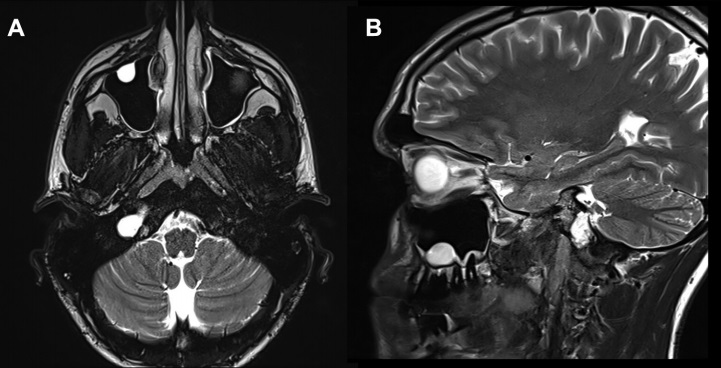

病情回顾:47岁的Emma突发性耳聋和右侧面部疼痛,曾以为是三叉神经痛导致,后检查考虑为岩尖区的胆固醇肉芽肿。增强MRI显示病灶在岩尖、耳蜗和内听道侧面和后部出现均匀强化病灶,T2低信号和T1高信号,病灶导致右侧内听道ICA和海绵窦向前移位(图A和B)。胆固醇肉芽肿是少见的囊性炎症病变,其特征是形成胆固醇晶体。它们是岩尖部较常见的病变,当出现症状时,可能会出现听力丧失、眩晕、耳鸣、头痛和面部病变。

▼术后(C、D)图像显示病灶次全切除,并显示鼻中隔瓣修复良好。显示岩尖然后面的小部分残留病灶(C、D、箭头)。值得注意的是,除了鼻中隔后三分之二和蝶窦外,全部其他鼻内正常组织结构均被保留完整无损。